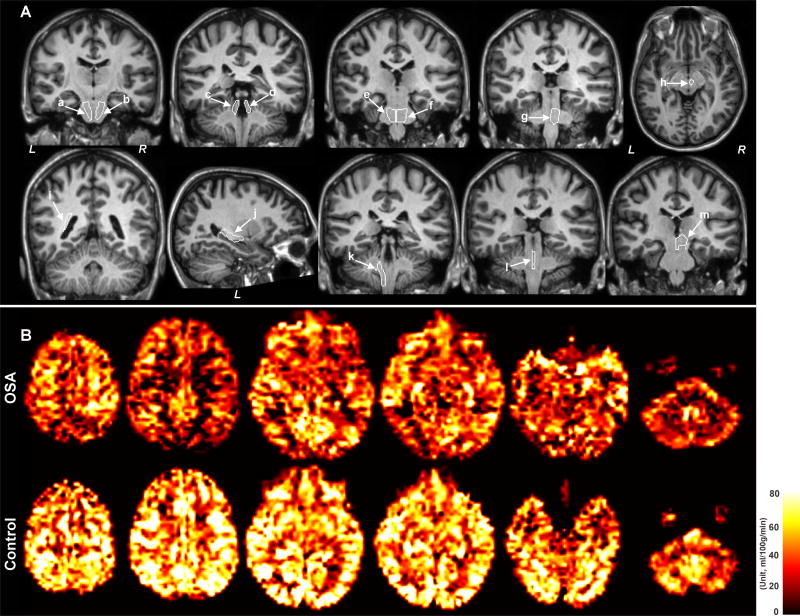

Significantly reduced regional CBF values appeared near multiple brain areas in OSA compared to control subjects (Table 1, Fig. 1A), but no sites showed significantly increased localized values in OSA over controls. Examples of whole-brain CBF maps from an OSA and a control subject are shown in Fig. 1B. Reduced CBF values in OSA appeared near the bilateral corticospinal tracts (right, p=0.009; left, p=0.04), superior cerebellar peduncles (right, p=0.02; left, p=0.03), and pontocerebellar fibers (right, p=0.01; left, p=0.05). However, unilateral reductions in CBF of OSA subjects appeared in the medial lemniscus (right, p=0.02), red nucleus (right, p=0.012), tapetum (left, p=0.04), dorsal fornix/stria terminalis (left, p=0.02), inferior cerebellar peduncle (left, p=0.02), and midbrain (right, p=0.05), compared to control subjects (Fig. 1A); reduced flow also appeared in the midline pons (p= 0.01)

Fig. 1.

(A) Regions of interest (ROIs) from different brain sites, overlaid onto T1-weighted images that showed significant bilateral and unilateral reduction of CBF in OSA. The bilateral areas included the corticospinal tracts (coronal; a, b), superior cerebellar peduncles (coronal; c, d), pontocerebellar fibers (coronal; e, f), and regions of unilateral CBF reduction, which included the right medial lemniscus (coronal; g), right red nucleus (axial; h), left tapetum (coronal; i), left dorsal fornix/stria terminalis (sagittal; j), left inferior cerebellar peduncle (coronal; k), midline pons (coronal; l), and right midbrain (coronal; m). All brain images are displayed in neurological convention, with the left side of brain represented on the left side of the image. (L = Left, R = right). (B) Examples of whole-brain CBF maps in an OSA (age, 55.7 years; male), and a control subject (age, 54.9 years; male). Warm colors indicate corresponding regional CBF values.